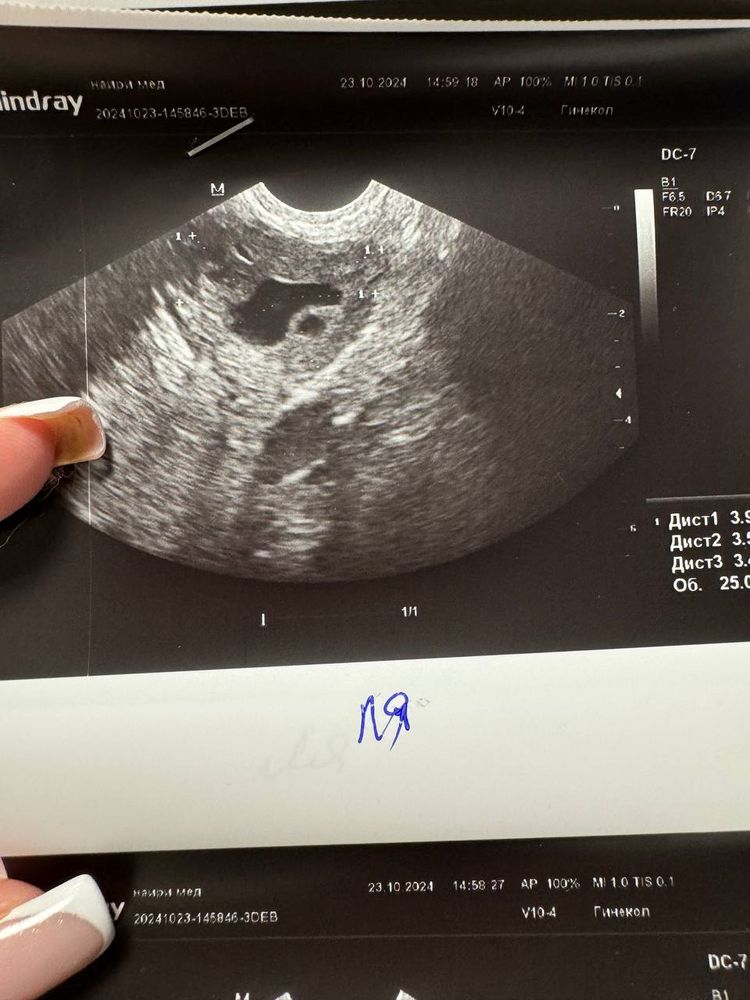

23.10.2024 - 7 день цикла, фолликул выглядит так(с разных ракурсов) и эндометрий 6,5